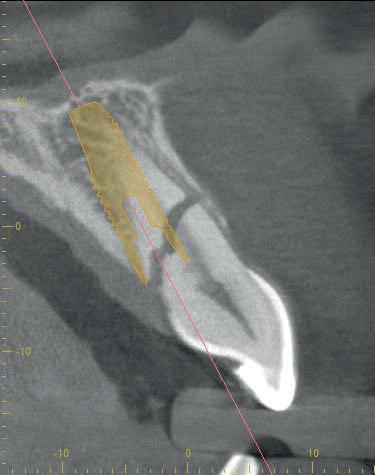

Casus

In deze casus is extractie van de 37 geïndiceerd in verband met een fistel en restpockets, zoals zichtbaar op de röntgenfoto’s (afbeelding 1). Duidelijk te zien is de forse peri-apicale ontsteking en het botverlies bij de 37, dat zowel richting buccaal als linguaal doorloopt. De 37 wordt atraumatisch verwijderd. Er is aan de linguale zijde veel bot verloren en er is sprake van een perforatie aan de buccale zijde.

Er wordt besloten om botmateriaal te plaatsen in de extractie-alveole. Vervolgens wordt het afgesloten met een titanium versterkt d-PTFE membraan (afbeelding 2). Na vier weken wordt het membraan verwijderd.

Zes maanden na extractie wordt het implantaat 37 geplaatst. Er is sprake van een goede genezing en de processushoogte en -breedte zijn behouden en opgebouwd. Ook is er zichtbaar gekeratiniseerd weefsel

1 2 Ridge preservation met d-PTFE membranen 35

gewonnen. De wond kan na het plaatsen van een healing abutment primair gesloten worden (Afbeelding 3a-3d).

In afbeeldingen 4a-c is het resultaat drie maanden na het plaatsen van het implantaat te zien. De genezing is volledig en de verwijzer kan de suprastructuur vervaardigen (afbeelding 4a-4c).

In afbeeldingen 5a-d is de implantaatkroon 37 te zien, twee jaar na plaatsing. Op de röntgenfoto is herstel van zowel corticaal als spongieus bot te zien. (De CB-CT was vervaardigd in verband met implantologische indicatie in het naastliggende gebied).

Deze casus illustreert dat er op een voorspelbare manier een ridge preservation procedure uitgevoerd kan worden met een d-PTFE membraan en er daarna voorspelbaar geïmplanteerd kan worden.